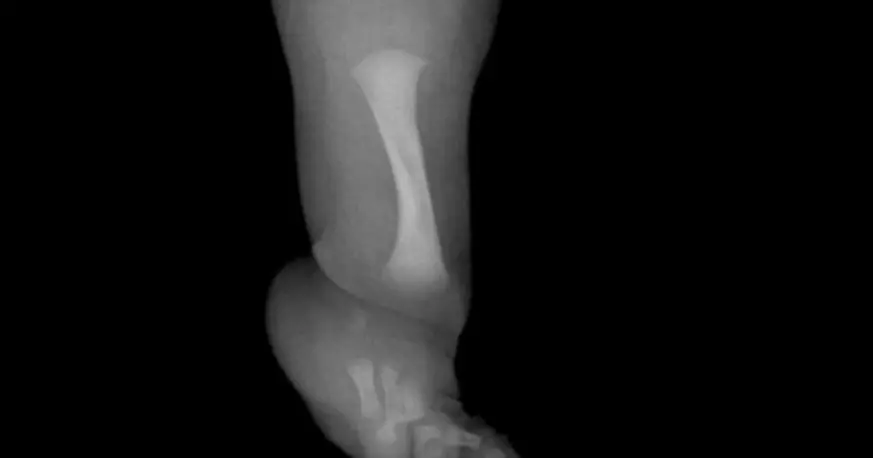

El niño fue diagnosticado con hemimelia fibular, una enfermedad congénita rara que afecta el desarrollo del peroné, uno de los huesos largos de la pierna. Esta malformación puede provocar diferencias en la longitud de las piernas, inestabilidad en la rodilla y el tobillo, y dificultades severas para caminar si no se trata a tiempo.

La patología se caracteriza por la ausencia total o parcial del peroné. Esto afecta no solo la estructura ósea, sino también el alineamiento de la pierna, el desarrollo del pie y la estabilidad de las articulaciones. En los cuadros más severos, el chico puede presentar pies deformados, cojera marcada y dolor crónico al intentar apoyar.